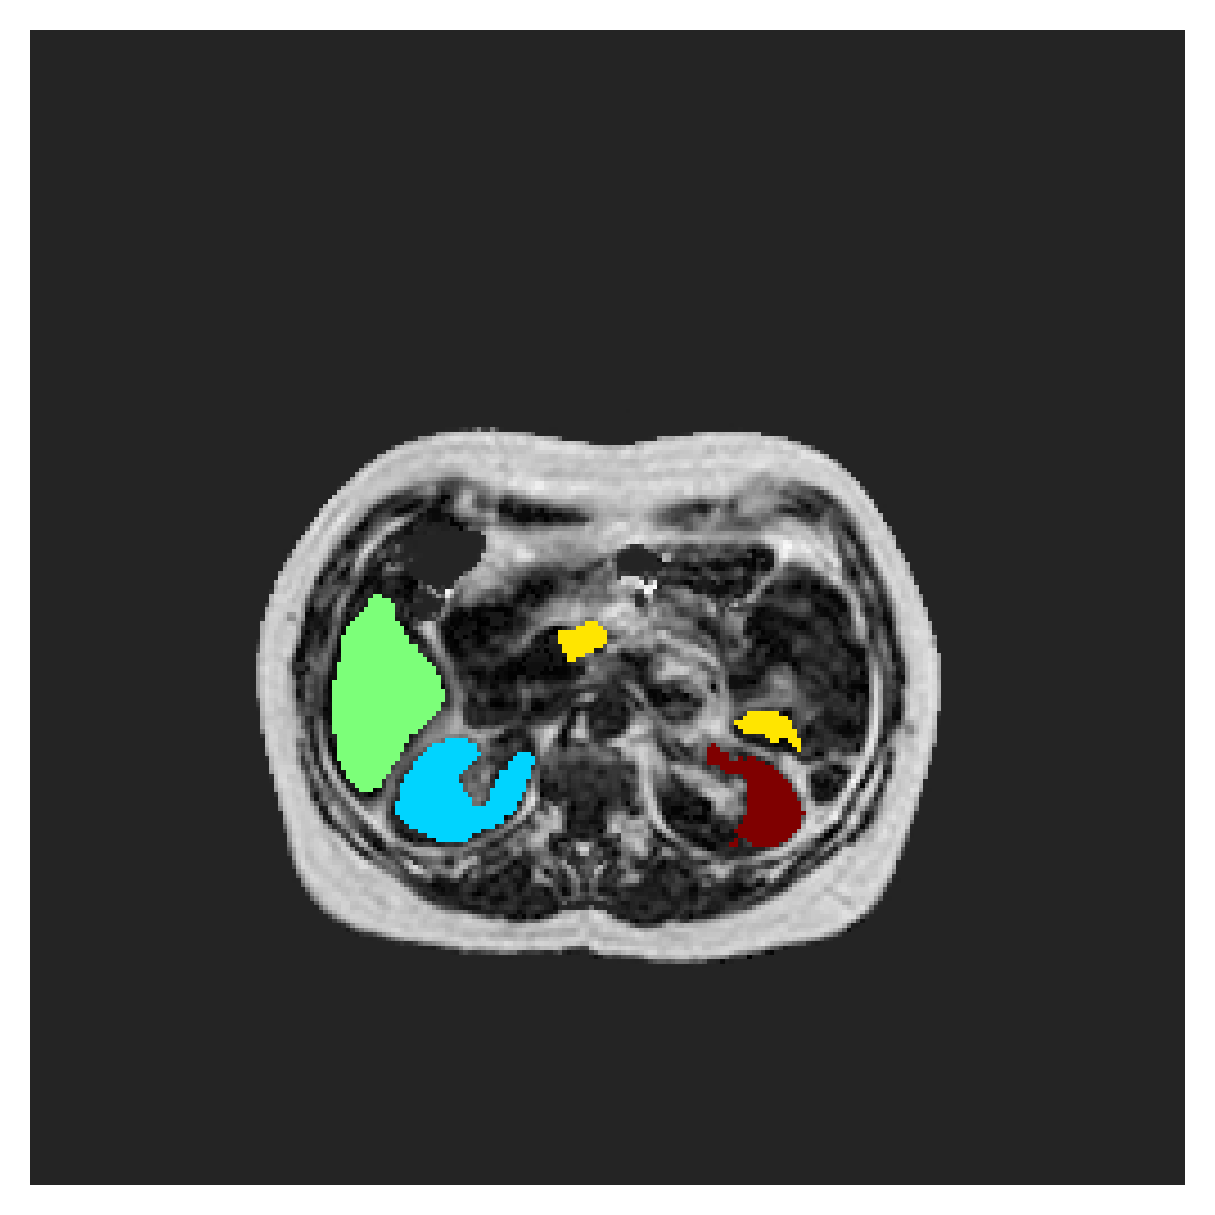

POEM

The Prospective investigation of Obesity, ENergy production and Metabolism (POEM) is a local (not currently publicly available; PI: L. Lind, see [22] for details) cohort of whole-body fat/water separated MR images. Full annotations of the liver, kidneys, bladder, pancreas and spleen are available for 50 subjects, providing a challenging segmentation dataset with heavily imbalanced classes of varying shapes. The resolution of the data is anisotropic, with reconstructed voxel size of in left-right, anterior-posterior and foot-head directions, respectively. For additional technical details regarding the acquisition and specifications of the images see [22].

The images contain two channels, one for water and one for fat content. For training, we normalize the volumes (per channel) and use 2D slices in the coronal plane, sized . The weak annotations are created synthetically, following the same procedure as described for the ACDC dataset.

5.2 Abdominal organ segmentation

Using 2D distance maps

In Table 3, the average DSC and HD95 results are shown (both using 2D and 3D distance maps) for the task of abdominal organ segmentation in POEM data (for boxplots see figures 8 and 9). We see that training with and (with distances calculated on 2D slices) performs comparably, while using and produces lower scores in both DSC and HD95 metric. On this dataset, the CRF-loss is able to compete with the boundary loss-based training strategies, even outperforming them on most classes. Most notably, all models trained with boundary loss appear to have a hard time segmenting the liver. We hypothesize this may be due to extremely severe class imbalance, as the liver covers a very large area compared to the rest of the classes. It is thus also more strongly affected by undersegmentations.

Using 3D distance maps

Inspecting the values of training with on distance maps computed in 3D from Table 3, we notice that the results generally improve over values achieved by using 2D distance maps. Most notable decreases are visible in HD95 values, as using volume-calculated distance maps provides more global information and additionally penalizes spatially unreasonable segmentations. The methods based on are now able to compete with the CRF-loss, in particular the one.

In Figure 10, the validation curve evolution is plotted. Comparing it to the one with using 2D-computed distance maps, in Figure 7, we see that the curves for all the methods training with improve, with the exception of based one. The lack of improvement here could be attributed to the MBD bleeding through object boundaries (due to noise) and propagating low distances further away in the volume, causing under-penalization. This is also suggested by the degradation in performance from 2D to 3D maps in Table 3. But at the same time, it allows for better segmentation of large and/or elongated (homogeneous) objects, which is also confirmed by the large improvement of liver segmentation scores in Table 3.

5.2.1 Qualitative comparison

In Figure 11 and 12 we show the same random slices in cases of calculating the boundary loss on 2D- and 3D-based distances, respectively. Comparing the two figures again indicates that the intensity-aware distances offer most improvement when calculated in 3D over 2D. The exception here is the MBD, which seems to even slightly degrade for most classes.